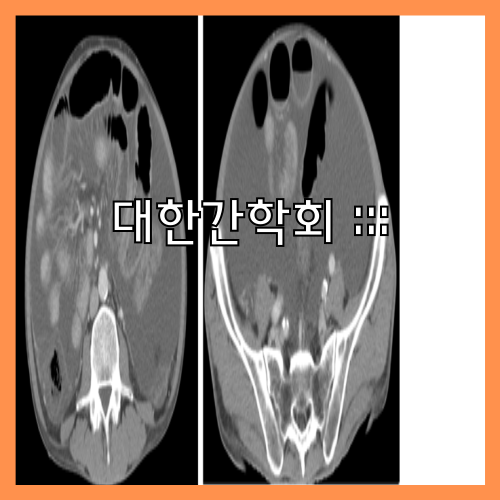

맹장염은 증상이 시작된 지 3일 이내에 수술을 받지 않으면 맹장이 터지기 때문에 병원에서 전문 치료를 받아야 합니다. 맹장이 터지면 충수 주위에 고름이 고이는 농양으로 발전해 복강 내 전체에 고름이 퍼지는 복막염이 생깁니다. 수술은 복잡해질 뿐 아니라 회복기간이 길어져 수술 후 패혈증과 장유착 등의 합병증이 생길 수 있습니다.